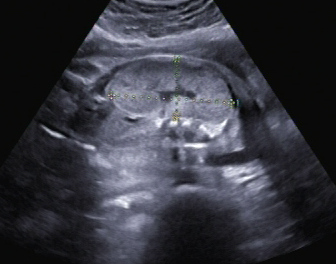

Ein zunächst durchgeführtes CTG war unauffällig. Im Rahmen der sonografischen Untersuchung zeigte sich der Fötus soweit beurteilbar zeitgerecht entwickelt. Dennoch konnte ein Anhydramnion festgestellt werden(Abb. 1, 2), weshalb auch kein fetales Gesicht darstellbar war (Abb. 3).